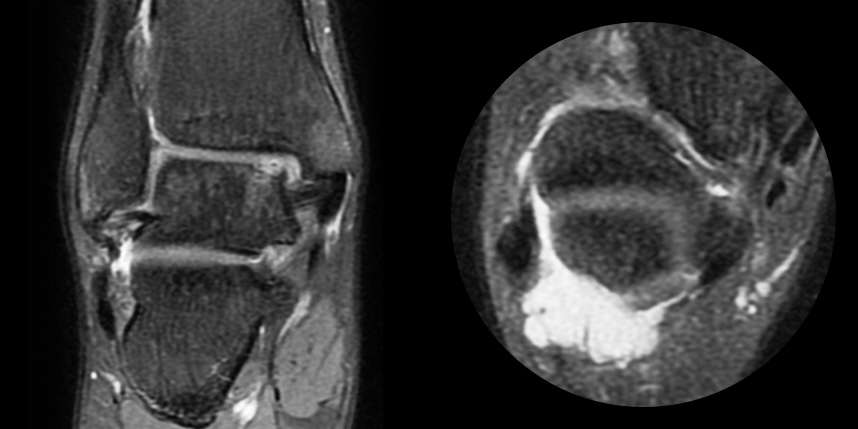

특수하게 농축하여 제작된 6% 콜라겐(리젠실603) 또는 9% 콜라겐(이엔카티)을 천공술을 시행한 부위에 덮어 주어 미세천공술 단독보다 좋은 치료 결과를 기대할 수 있습니다.

동종 제대혈줄기세포를 이용하여 연골 재생을 촉진하는 방법으로 초자연골에 가까운 연골로 재생되는 것을 기대할 수 있습니다.

본원에서는 미세천공술, 콜라겐주입술, 카티스템 치료를 주로 하고 있습니다.

연골 재생 상태를 확인해야 합니다.

타병원 미세천공술 실패 후 통증으로 내원하신 사례

* 환자에게 받은 소중한 자료입니다.